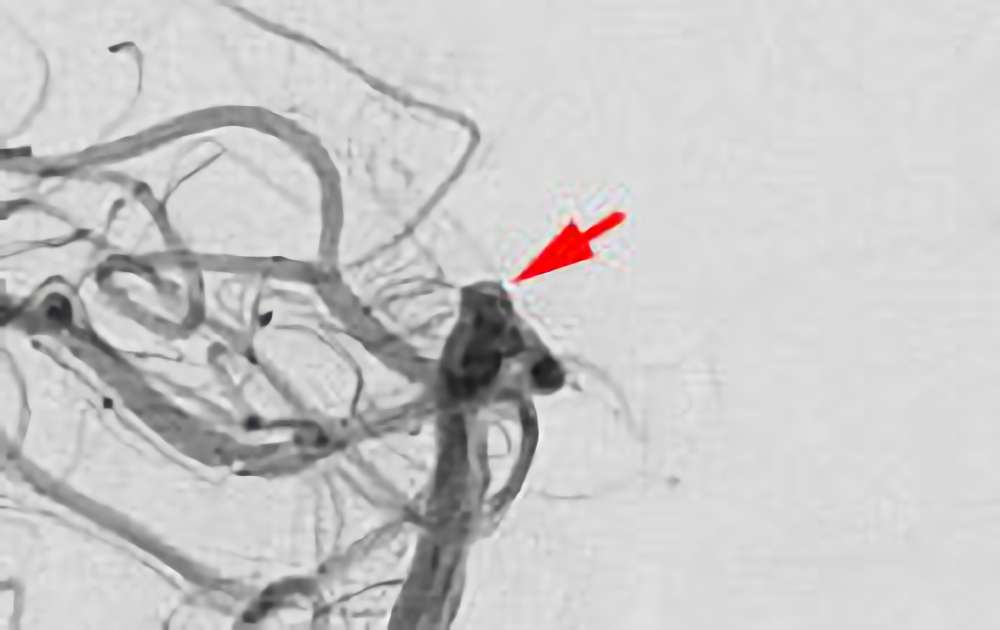

No.1600 手術前

No.1600 手術中

No.1600 手術後

くも膜下出血

脳底動脈瘤破裂

40代

救急外来